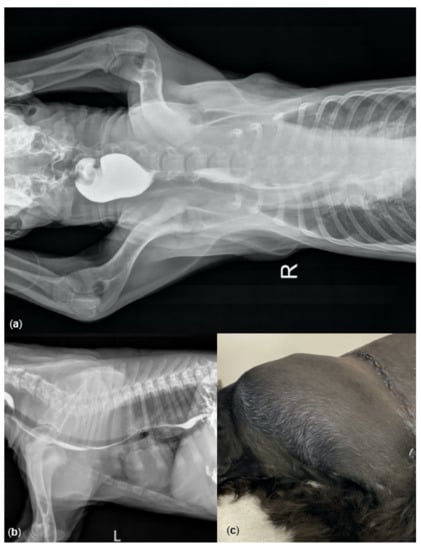

| 1 | 17 | 30/ND | 240/11 | Admission, dyspneic |

| 2 | 08 | 13/5.0 | >300/11 | Progressive dyspnea, ventilated |

| 10 | ND/ND | 162/ND | Post pRBC transfusions ** | |

| 14 | 18/5.0 | 133/ND | Post thoracic surgery and FFP transfusion | |

| 23 | ND/ND | 135/ND | Post additional FFP transfusion | |

| 3 | 07 | 20/6.0 | ND/ND | Clinically stable |

| 4 | 14 | 24/5.0 | 126/11 | Clinically stable |

| 5 | 10 | 35/7.0 | 124/ND | Prior to FFP transfusion ** |

| 22 | 34/8.0 | 129/ND | Post FFP transfusion | |

| 6 | 10 | ND/ND | 105/ND | Post FFP transfusion |

| 10 | 08 | 41/8.0 | >300/ND | Severe chest wall hematoma |

| 11 | 10 | 20/6.0 | ND/ND | Euthanasia |